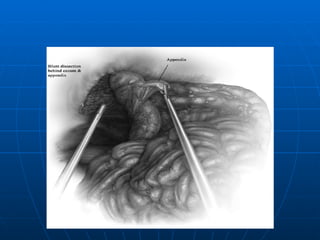

TRATAMIENTO LAPAROSCOPICO Excelente Iluminación y exposición del campo operatorio Disminución de Complicaciones Mayor costo (equipos- anestesia general) Mayor tiempo Operatorio ( 3 Trócares umbilical,suprapúbico (10mm y fosa iliaca izquierda 5mm). En todos los grupos cuando el Apéndice es normal  no se extrae (no así en las convencionales)

TRATAMIENTO CONVENCIONAL APENDICECTOMIA:1.- Localización del apéndice 2.- Transección del meso (arteria) 3.- Sección de la base (coprostasia) 4.- Manejo del Muñon( ligadura simple, inversión o combinación de ambos,pto. En Z o jareta) APENDICECTOMIA RETROGRADA PLASTRON APENDICULAR (Muñon libre + Drenaje) PERITONITIS DIFUSA (Lavado Peritoneal) APENDICE NORMAL

TRATAMIENTO LAPAROSCOPICO ExcelenteIluminación y exposición del campo operatorio Disminución de Complicaciones Mayor costo (equipos- anestesia general) Mayor tiempo Operatorio ( 3 Trócares umbilical,suprapúbico (10mm y fosa iliaca izquierda 5mm). En todos los grupos cuando el Apéndice es normal no se extrae (no así en las convencionales)